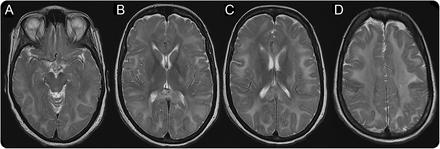

神经影像学研究结果缺乏硫胺转运体

神经影像学研究SLC19A3基因突变。(模拟)轴向大脑MRI披露明显扩散hyperintensity深远的和大脑皮层下白质和皮质脊髓束hyperintensity内囊后肢的t2加权图像。